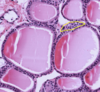

Bile canaliculi - Bile is secreted into bile canaliculi (BC). These channels are formed by the retraction of

the plasma membranes (arrows) of the hepatocytes to produce an open space between adjacent cells. Thus, bile canaliculi are not channels lined by a cell population distinct

from hypatocytes, but are an anastomosing series of tunnels lined y the hepatocytes themselves. Microvilli from the surface of the hepatocytes that form the bile canaliculus entre the channel. Tight junctions (arrowheads) between the hepatocytes seal off the area and prevent leakage of bile into the intercellular spaces.